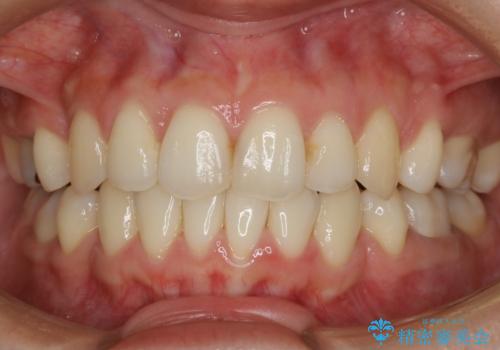

【抜歯】口元を引っ込めたい ワイヤー矯正

- 20代 女性

- ワイヤー(クリア装置)

- 2年6ヶ月

- 30回以上

しっかりと口元・顔貌まで変化を起こせるように上下左右の第一小臼歯を抜歯し、ワイヤー装置にて矯正を開始することとなりました。

- 税込¥990,000 (ワイヤー装置+マイクロインプラント費用)費用は治療当時の料金となります